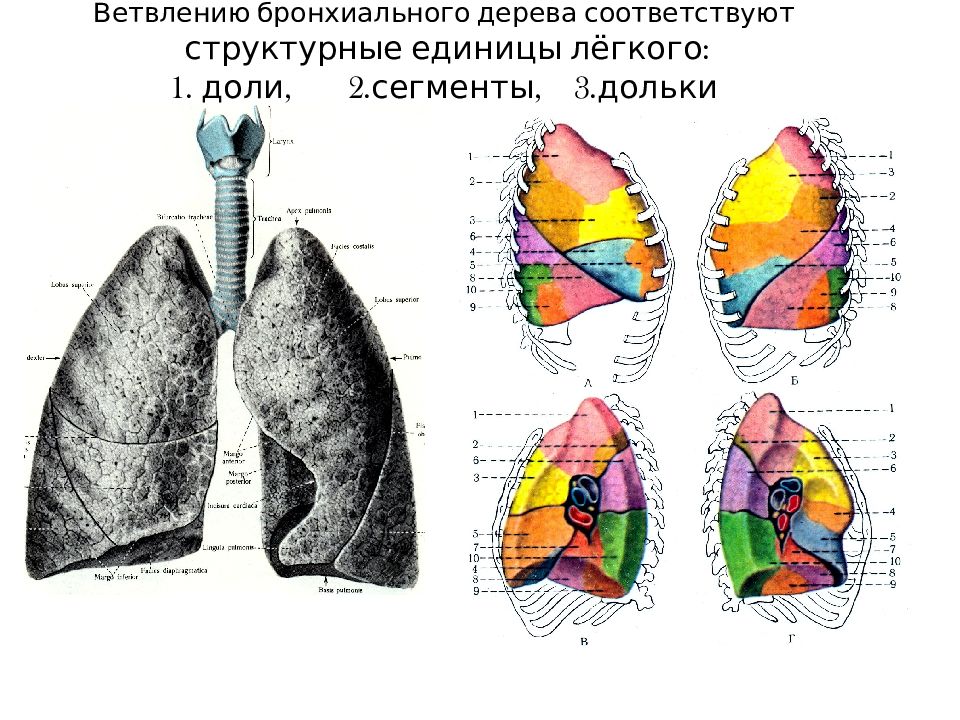

Анатомические изображения сегментов легких различных животных

Раздел: Другие животные